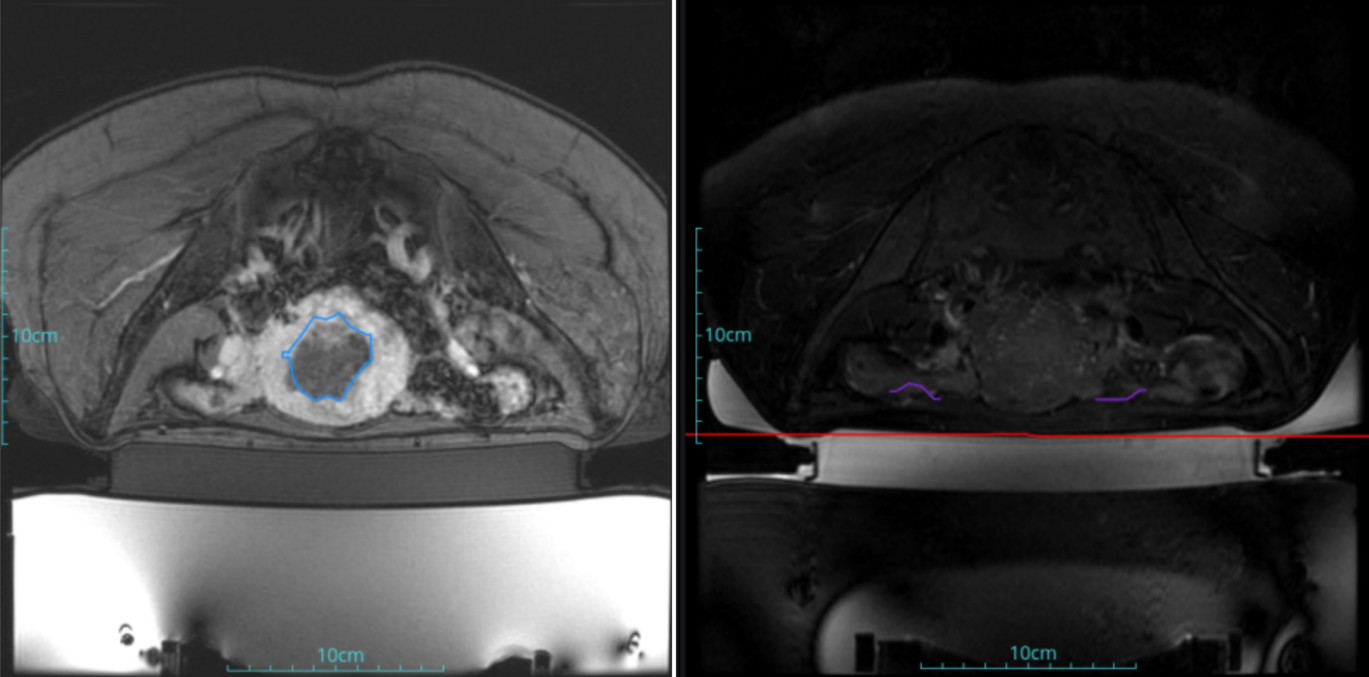

Adenomyosis

Patient Information:Female,38

Diagnosis: adenomyosis

Tumor size: about 40*37*40mm

ROT depth: The ROT center of the tumor is 45mm from the skin

Postoperative evaluation: Postoperative enhanced imaging showed a good overlap between the ablation area (right) and the lesion area (left), the non-perfusion area was continuous and consistent.

Conclusion:It has a excellent ablation effect on this lesion, and the temperature rise curve during treatment is in line with expectations. The 240CEM area of each treated target is large, full and continuous.The ablation effect was good,the NPV volume ratio was about 80.6%.